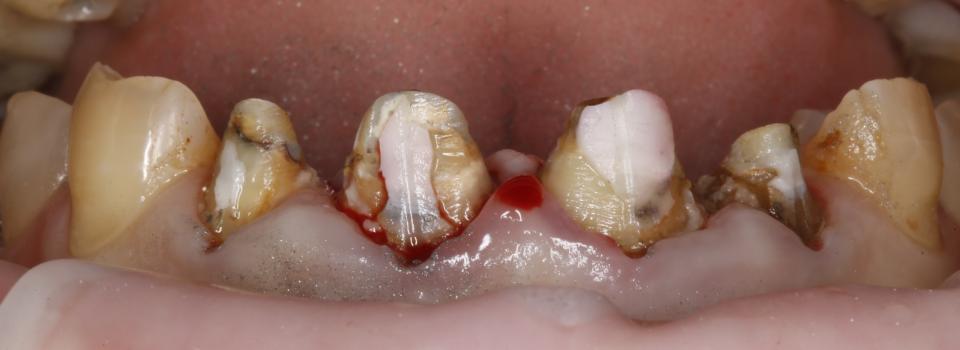

paraschyk1 Опубліковано: 6 червня 2018 Автор Опубліковано: 6 червня 2018 Вот фото зубов где коронки были сделаны пять лет назад с прайсом вдвое дороже чем у меня сейчас. Зубы после такого- трупы.А все от ненадлежащего качества работы и пох.зма в отношении в людям.

paraschyk1 Опубліковано: 6 червня 2018 Автор Опубліковано: 6 червня 2018 Вот фото где также коронки простояли четыре года и пац только выплатил кредит по ним,а спустя два мес. пришлось все убрать и переделывать,ессно за новые тугрики.